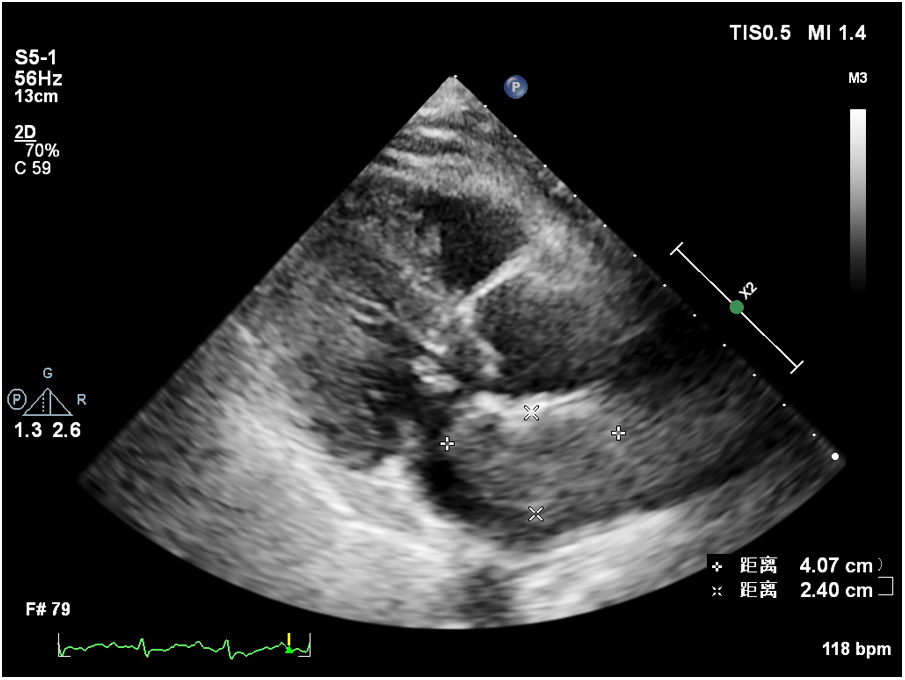

At 8 months post-surgery, a 41 × 24 mm mass in the left atrium was detected using transthoracic echocardiography. The lesion had an irregular shape, uneven echogenicity, and an ill-defined boundary with the atrial septum. The maximum velocity of blood flow through the mitral valve was measured to be 1.39 meters per s. The maximum and mean pressure gradients across the valve were found to be 8 and 4 mmHg, respectively. During the contrast-enhanced ultrasound examination, perfusion of the contrast agent was observed in the mass. However, the enhancement degree was lower than that of the adjacent myocardium, leading to the diagnosis of tumor recurrence. (Figure 4, Supplementary Video 2). Considering tumor recurrence, Lenvatinib Mesylate was added as an anti-tumor therapy. The patient was followed up monthly in our hospital. Having gone through the series of treatments (Table 2), she complained of nothing but feeling a little weakness with firm support from family members and meticulous care from medical staff, she kept an Optimistic attitude.

Figure 4

Recurrent tumor in the left atrium.

Left atrial myxofibrosarcoma is usually characterized by low or moderate echogenic masses attached to the left atrial valve or wall (3). These lesions often exhibit unclear boundaries from surrounding normal tissue, irregular shapes, and uneven echogenicity. Additionally, they are frequently large, sessile, and possess a broad base. They may also invade the pulmonary veins and exhibit other features. In the present case, one of the masses oscillated around the mitral valve orifice during the cardiac cycle, obstructing the valve orifice during diastole. This resulted in symptoms of mitral stenosis, such as chest tightness and dyspnea. Distinguishing left atrial myxofibrosarcoma from left atrial myxoma is crucial. The American Society of Echocardiography guidelines recommend the differentiation of intracardiac masses using ultrasound enhancement agents (8). Benign cardiac tumors, predominantly myxomas, typically exhibit sparse neovascularization, with the myxoid matrix composed of acidic mucopolysaccharides (9, 10). In contrast, malignant tumors, such as myxofibrosarcomas, grow rapidly and feature abundant new blood vessels, densely distributed with a dilated lumen, resulting in significant enhancement during angiography (11). Of note, conventional ultrasonography revealed that the mass had an irregular shape, uneven echogenicity, no peduncle, and a wide base, which required differentiation from a thrombus. Of note, thrombi do not exhibit enhanced imaging due to a lack of blood vessel supply, a feature distinguishing them from malignant tumors (8, 12). Postoperatively, a follow-up transthoracic echocardiography was conducted 8 months later, unveiling the recurrence of the tumor in the left atrium. Further characterization through contrast-enhanced ultrasound indicated sparse enhancement of the left atrial mass, with the degree of enhancement lower than that observed in the surrounding myocardium.

This observation contrasts with the preoperative contrast-enhanced ultrasonography, which demonstrated significant enhancement in the mass akin to the adjacent myocardium. The altered enhancement pattern may be attributed to the effects of chemotherapy and Lenvatinib Mesylate. Lenvatinib Mesylate is a tyrosine kinase (RTK) receptor inhibitor that inhibits the kinase activity of the vascular endothelial growth factor (VEGF) receptors VEGFR1(FLT1), VEGFR2(KDR) and VEGFR3(FLT4). Moreover, it also inhibits RTKs involved in other proangiogenic and tumorigenic pathways, including fibroblast growth factor (FGF), receptors FGFR1, 2, 3, and 4, and platelet-derived growth factor (PDGF) receptors PDGFRa, KIT, and RET.